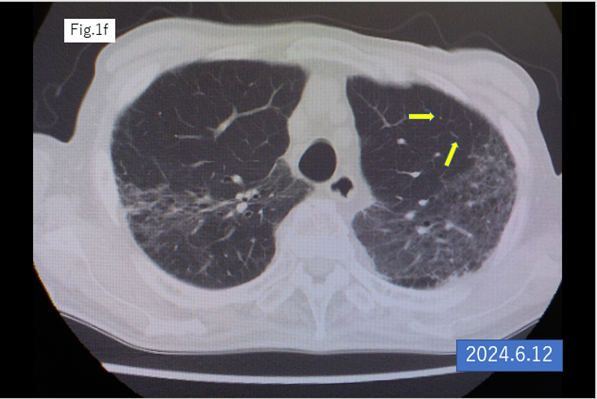

An 87-year-old male underwent laparoscopic left hemicolectomy for adenocarcinoma of the descending colon in December 2021. Lung metastasis was found in the left upper lobe 6 months postoperatively, and it increased in size after 9 months from the surgery. S-1 plus oxaliplatin (SOX) was started in October 2022. The lung metastasis was shrinking within 23 cycles of SOX therapy. The 24th cycle of SOX (only oxaliplatin) was administrated in April 2024, the catheter of venous infusion line of right forearm was removed after finishing the infusion, however bleeding did not stop. The platelet count was rapidly dropped into 2,000/μl from 131,000/μl (pretreatment) within 7 hours and hemoglobin levels decreased from 10.9 to 8.9 in the same period, furthermore, dropped into 6.2 g/dl in next 24 hours. PA-IgG was significantly high (204.0 ng/107 cells; normal < 30.2). Transfusion of platelet, red blood cell concentrate, steroid pulse therapy, antibiotic treatment with multiple agents and non-invasive positive pressure ventilation (NPPV with oxygen were performed. As a result, the patient’s platelet count was increased and his DIC score was decreased to 3 points (normal range) in April 2024. The patient’s general condition gradually improved, and he was discharged from hospital on the 35th day of hospitalization. CT scan after discharge showed complete remission of the lung metastasis. Possible mechanisms and approach to treatment are discussed.

An 87-year-old male underwent laparoscopic left hemicolectomy with a diagnosis of adenocarcinoma of the descending colon in December 2021. Lung metastasis was found in the left upper lobe 6 months postoperatively, and it increased in size after 9 months from the surgery (Figures 1a,b). The patient began S-1 plus oxaliplatin (SOX) treatment with first-line chemotherapy consisting of oral S-1 (a mixed drug of tegafur, gimeracil, and oteracil potassium) at a dose of 50 mg twice daily for 2 weeks following by 1-week off schedule, and intravenous oxaliplatin (100 mg/m2) given on day 1 of a 3-week cycle [2,3], was started in October 2022.The lung metastasis was shrinking within 23 cycles of SOX therapy (Figures 1c–f). The 24th cycle of SOX (only oxaliplatin) was administrated in April 2024, the catheter of venous chemotherapy line of right forearm was removed after finishing the infusion, however bleeding did not stop. The patient had vomiting, chill and pale face, and was transferred to the intensive care unit. The platelet count was rapidly dropped into 2,000/μl from 131,000/μl (pretreatment) within 7 hours and hemoglobin levels decreased from 10.9 g/dl to 8.9 g/dl in the same period, furthermore, dropped into 6.2 g/dl in next 24 hours. Disseminated intravascular coagulation (DIC) score was 8 points, and platelet-associated IgG (PA-IgG) was significantly high (204.0 ng/107 cells; normal < 30>.

Figure 1: CT scan of the lung

Allergic hypersensitivity has been reported to occur in 10–23.8% of patients who have undergone oxaliplatin therapy, known as a type I hypersensitivity reaction involving IgE mediated release of antibodies, is well known complication and is usually well-managed with using steroid [9-11]. Oxaliplatin-induced ITP, as shown by our case, is a type II hypersensitivity reaction involving release of IgG antibodies binding tos platelet surface [12-15]. These two types of allergic reaction are known as oxaliplatin induced immune syndrome (OIIS) and the latter, as shown in the present case, has been reported to present hyperacute thrombocytopenia is recommended to be treated with steroid pulse therapy and platelet transfusion. In the present case, although DIC score was high and sufficient for DIC diagnosis, anticoagulation therapy was not selected but steroid pulse as well as infusions of platelets and concentrated red blood cells were performed, and alveolar bleeding and pneumonia were successfully managed followed by recovery. Although no anticancer therapy was administered since the onset of thrombocytopenia, the nodule of lung metastasis was disappeared after the recovery, and the mechanisms of this anti-tumor reaction are not clear. Given that oxaliplatin has been reported to induce immunogenic cell death in the tumor microenvironment [16,17], anti-tumor immune reactivities including in immunological memory may exist, and some mechanisms of immunosuppression might be altered by chain of immunological events occurred to this patient.